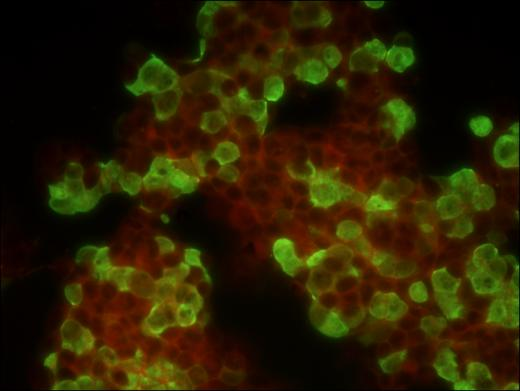

Hình Ảnh Sắc Nét, Quan Sát Chính Xác

Nhờ sử dụng hệ quang học Infinity plan achromatic objectives, MF31 cho hình ảnh sắc nét đến từng chi tiết nhỏ nhất. Đặc biệt, độ chính xác màu sắc và độ tương phản cao giúp người quan sát nhận diện mẫu vật dễ dàng hơn, ngay cả với những mẫu có độ phát huỳnh quang yếu.

- Bộ lọc huỳnh quang: Blue, Green, UV,… tùy theo ứng dụng

- Quan sát mô bệnh học và tế bào học